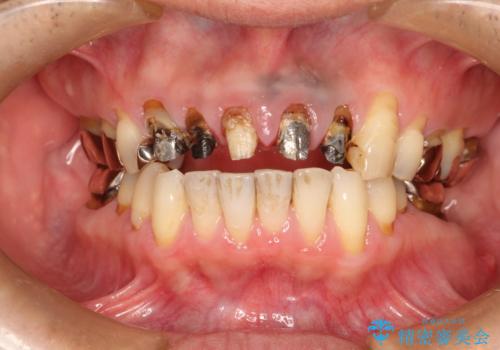

上の前歯の根元が黒い 根の治療を含めたセラミック再治療

- 上の前歯の根元が黒くなっているので、再治療をしたいとのことで来院された患者様です。

レントゲンを撮影すると、適合不良のかぶせ物が装着されており、根の治療も不十分であることが確認されました。

適合不良のかぶせ物をすべて除去して、根の中の治療から再治療を行うこととなりました。

適合不良のかぶせ物が装着されていた歯は、内部がやはり虫歯になっていました。

かぶせ物だけではなく見えないところも、精密な治療をすることが重要となります。